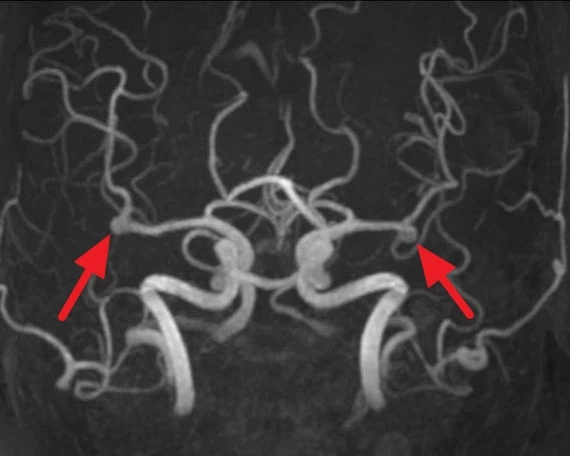

특히 뇌동맥류가 두 번 이상 터질 경우에는 70~80%에서 심한 후유증을 남기거나 생명을 잃게 됩니다. 뇌동맥류가 터지기 전에 CT 조영 촬영(CTA)이나 MRA를 촬영하면 약 95%이상에서 뇌동맥류를 발견할 수 있습니다. 치료 방법을 결정하기 위한 가장 중요한 검사는 뇌혈관 촬영인데 1-2일 정도 입원이 필요합니다.